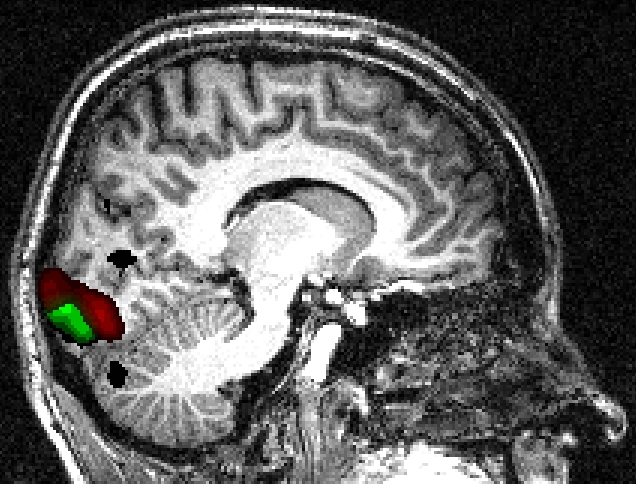

Retinotopic mapping of human visual cortex using fMRI is a well established method (Sereno et al. (1995); Warnking et al. (2002)) that allows to properly delineate low visual areas. It uses four separate experiments with 4 periodic stimuli (an expanding/contracting ring and a rotating counter or anti-counter clockwise wedge) to measure respectively eccentricity and polar angle maps. For this study, we only used functional MRI data corresponding to the expanding ring experiment (240 volumes acquired each 2 seconds). The periodic visual stimulus expanded from 0.2 to 3 degrees in the visual field during 32 seconds and was repeated fifteen times. This periodic stimulation generated a wave of activation in the retinotopic visual areas (Engel et al. (1994)), located in the occipital lobe, at the frequency of 1/32 Hz measured at a discrete temporal sampling of 2 seconds (equivalent to 1/16 temporal bins). After IC analysis of these functional data, using our R function \codef.icast.fmri.gui(), 18 and 15 components were automatically extracted respectively with tICA and sICA. In this experiment, we searched for components corresponding to cortical activation at the frequency of the visual stimulation. tICA and sICA extracted more (noisy) components than the ones specific to the stimulus. Indeed, the main problem with fMRI data is that each activated voxel of each volume contains a mixture of the signal of interest (BOLD effect) with several confound signals with several origins: ocular movement, heart rate, respiratory cycle, or head movement. Figure 10 shows the temporal and spatial components at the frequency of the visual stimulation corresponding to the cortical activation of interest. The computed phases are (approximatively) respectively equal to , and for tICA (green, red and blue components) and and for sICA (green and red components). Figure 10 displays on the corresponding anatomical image the cortical localization of these extracted components. For tICA and for each temporal component, this is done by selecting in the associated column of the estimated mixing matrix (see equation (4)) the most active voxels, defined arbitrarily (see Beckmann and Smith (2004) for another approach) as those whith a value above the 95% quantile (in absolute value). For sICA, we also thresholded arbitrarily each component at the 95% quantile. Based on the retinotopy property of the visual system, the expanding ring generates a cortical activation wave moving from the posterior part to the anterior part of the occipital lobe. As indicated in Figure 10 the computed phases of the extracted components increase as expected from the posterior to the anterior part of the occipital lobe.

![]() |

||

|||

As shown in Figure 12, the voxels containing the components extracted using temporal and spatial ICA were localized as expected in the same ventral cortical region, called V4-V8, known to be sensitive to color perception (Wade et al. (2002)).